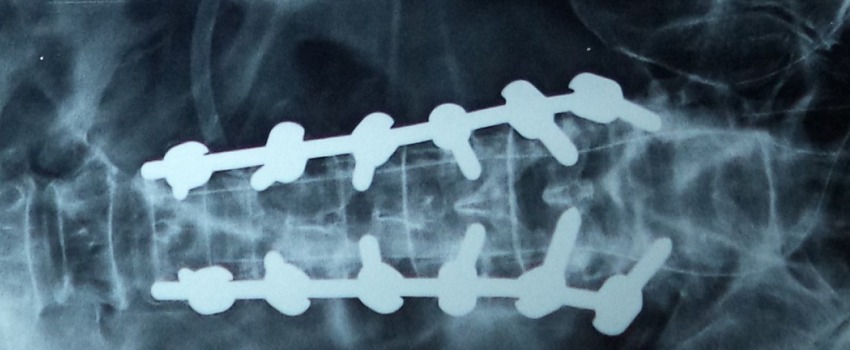

These fractures can be treated very well with the help of Pedicular screw system. This system and the C arm image intensifier equipment are very useful to correct and fix these vertebral fractures in the best possible position. After the spinal fixation, it is possible for the patients to sit and walk very early and the fixation gives very good pain relief.